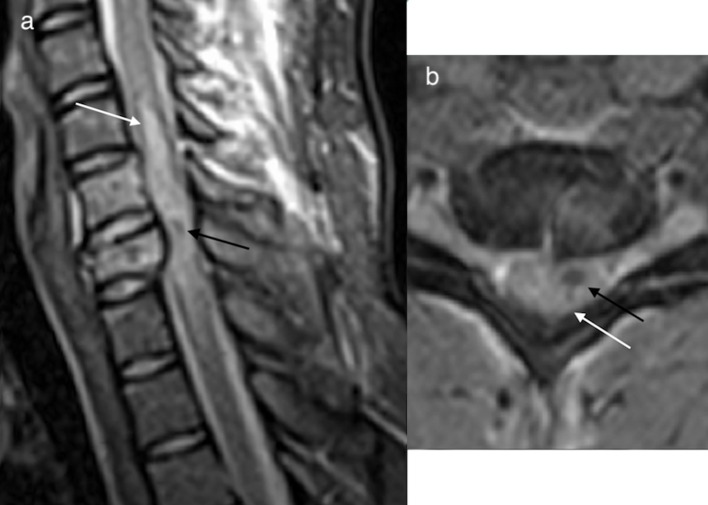

Intramedullary haemorrhage (haematomyelia) most often occurs where a patient has been subject to trauma.1 The haemorrhage tends to occur at the point of maximal impact and usually involves the central grey mater, occurring as a result of haemorrhagic necrosis of the cord.12 Axial T2* imaging is recommended for identification of intramedullary haemorrhage, which may be seen as a foci of hypointense signal on T2*. Intramedullary haemorrhage (Figures 10 and 11 black arrows) is frequently accompanied by cord oedema, (Figures 10 and 11 white arrows) seen as hyperintensity on T2 sequences, with loss of the grey white matter differentiation.4,12

Figure 10.

Sagittal T2 STIR image (a) and axial T2 GRE image (b) of the cervical spine demonstrating extensive cord oedema (white arrow) with intramedullary haemorrhage (black arrow) which is often seen in the presence of intramedullary haemorrhage. Intramedullary haemorrhage is seen as a foci of hypointense signal usually within the central grey matter of the cord. GRE,gradient echo; STIR, short tau inversion-recovery.

Figure 11.

Axial T2 (a) demonstrates cord swelling and oedema (white arrow) and axial GRE (b) shows intramedullary haemorrhage (black arrow). GRE,gradient echo.